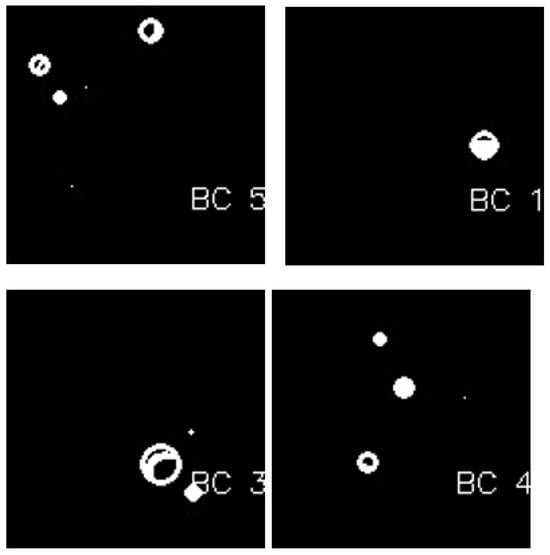

- The active contours method uses the obtained binary masks from the connected components analysis to highlight and isolate the edges/boundaries of ROIs. Further, the blob detection method is used to resolve undersegmentation from the previous step and identify BC lesions (blobs) from the previously obtained masked images.

3.4. Detection